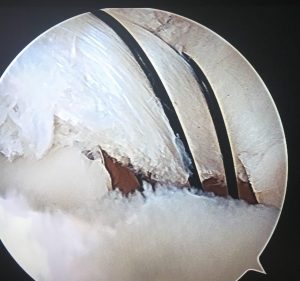

٣- دوره فلوشيپ ٧ ماهه در سال ١٣٧١ در دانشگاه McGill مونترال كانادا در جراحيهاي زانو و آرتروسكوپي Arthroscopy در بيمارستانهاي رويال ويكتوريا و بيمارستان عمومي مونترال و ملكه اليزابت

٤- فلوشيپ مهمان : ارتروسكپي و ارتوپدي ورزشي

Arthroscopic surgery and sports medicine

٥- فلوشيپ يكساله در جراحي باز سازي بالغين شامل فلوشيپ تحقيقات مفاصل و تعويض مفاصل hip and knee arthroplasty در موسسه راتمن ، در دانشگاه توماس جفرسون فيلادلفيا ، آمريكا

جراحيهاي آرتروپلاستي و تعويض arthroplasty مفصل شانه از بيمارستان Methodist متديست فيلادلفيا . ١٣٨٦الي ١٣٨٧